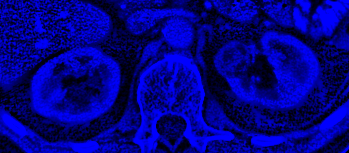

Blue Channel: Texture Variance

Blue Channel Image

Micro-Texture Extraction

Applies non-linear filters to isolate micro-textures, separating cohesive benign tissue from chaotic, malignant growths.